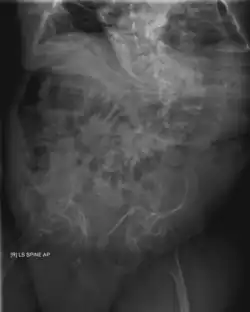

Diagnosis is typically based on medical imaging, including plain X-rays, and symptoms. In severe OI, signs on medical imaging include abnormalities in all extremities and the spine.[97] As X-rays are often insensitive to the comparatively smaller bone density loss associated with type I OI, DEXA scans may be needed.[5]: 1514

An OI diagnosis can be confirmed through DNA or collagen protein analysis, but in many cases, the occurrence of bone fractures with little trauma and the presence of other clinical features such as blue sclerae are sufficient for a diagnosis. A skin biopsy can be performed to determine the structure and quantity of type I collagen. While DNA testing can confirm the diagnosis, it cannot absolutely exclude it because not all mutations causing OI are yet known and/or tested for.[83]: 491–492 OI type II is often diagnosed by ultrasound during pregnancy, where already multiple fractures and other characteristic features may be visible. Relative to control, OI cortical bone shows increased porosity, canal diameter, and connectivity in micro-computed tomography.[98] OI can also be detected before birth by using an in vitro genetic testing technique such as amniocentresis.[99]